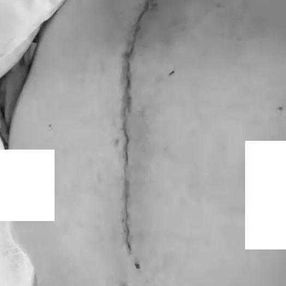

6. Drainage tubes were indwelt and the incisions were sutured.